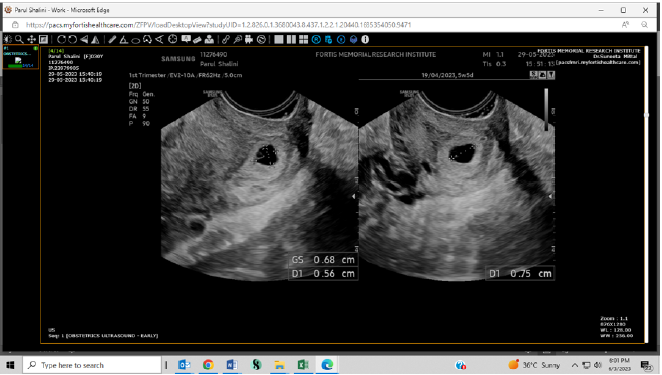

Successful Management of Cervical Ectopic Pregnancy

Suneeta Mittal and Deepika S Hooda. 12(7): 57-62.